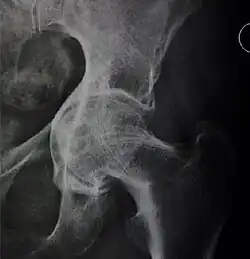

![Figure 5 (b). Coxa profunda.[3]](./_assets_/X-ray_of_coxa_profunda.jpg)